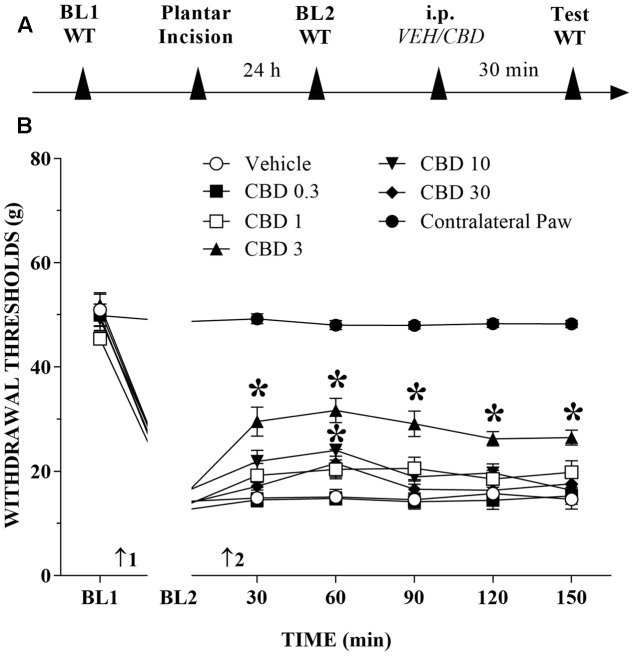

The timeline of the protocol for this experiment is shown in Figure 1A. Before incision of the hind paw, the withdrawal reflex was elicited by the application of approximately 50 g of force, using the electronic von Frey apparatus. In the incision pain model, we observed decreased mechanical thresholds, referred to as mechanical allodynia. The mean threshold measured 24 h after surgery decreased approximately 65% from the presurgical threshold, thus revealing the presence of mechanical allodynia. The systemic injection of CBD (0.3 to 30 mg/kg) produced a bell-shaped dose-related reduction of mechanical allodynia that lasted for at least 150 min at the 3 mg/kg dose. The decrease of mechanical allodynia was maximal at 60 min after the 3 and 10 mg/kg doses, which elicited a significant increase in the force required for paw withdrawal. The differences were statistically significant in terms of time [F(6,534) = 524.0; p < 0.01], treatment [F(6,89) = 149.2; p < 0.01] and the time × treatment interaction [F(36,534) = 45.2; p < 0.01]. The threshold of the non-incised hind paw did not change throughout the period of observation (Figure 1B).